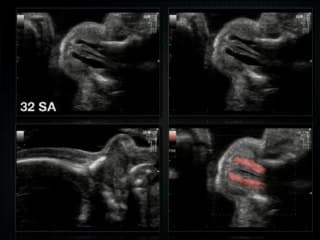

Démonstration live sur le placenta : localisation, structure, insertion funiculaire, usage du doppler couleur.